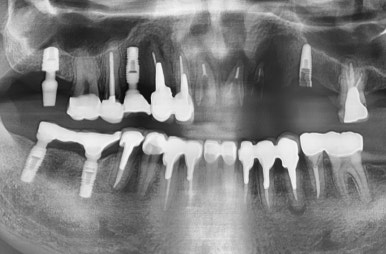

다른 치과에서 한 임플란트가 두개 묶여 있는데

흔들거리는 상태였습니다.

하나는 임플란트 주변 뼈가 많이 녹아서 흔들리고

다른 하나는 아래 사진처럼 임플란트 픽스쳐 안에 스크류가 파절되어있었습니다.

두 임플란트 쓸 수 없는 상태이므로

저희 치과에서 제거 하였습니다.